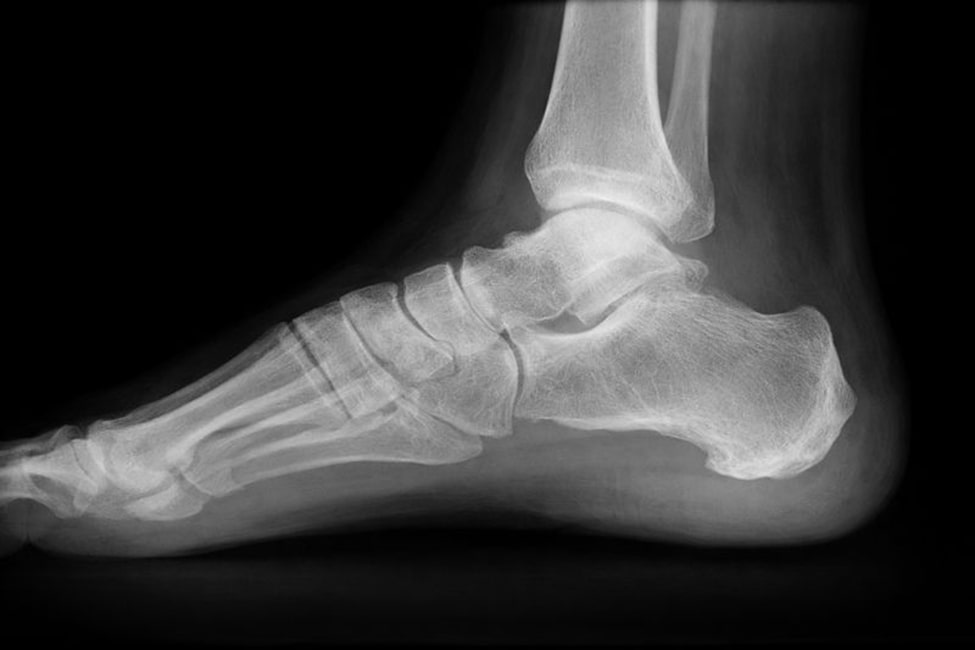

Рентгенография пяточной кости — это метод лучевой визуализации, при котором с помощью рентгеновского излучения получают изображение костных структур заднего отдела стопы. В ходе обследования фиксируется состояние пяточной кости, что позволяет оценить ее анатомические особенности, форму и положение относительно других элементов стопы. Обследование направлено на изучение плотности костной ткани, целостности структуры и возможных изменений, связанных с травмами, воспалительными процессами или дегенеративными нарушениями.

Рентген пяточной кости позволяет детально оценить целостность костной ткани и общее состояние пяточной кости, выявить трещины, деформации и изменения ее структуры. На полученном изображении могут визуализироваться различные патологические признаки, включая костную шпору, которая нередко становится причиной хронической боли при нагрузке на стопу. Также на снимке могут определяться проявления воспалительных процессов, участки уплотнения костной ткани или последствия ранее перенесенной травмы.

Метод дает доктору возможность выявлять патологические изменения, влияющие на анатомическое положение кости, распределение нагрузки при ходьбе и опоре на ногу. Благодаря этому врач получает объективную информацию, необходимую для уточнения диагноза, оценки степени выраженности изменений и выбора дальнейшей тактики наблюдения или лечения.

Чаще всего используется боковой вариант укладки, который позволяет получить наиболее информативное изображение пяточной кости и окружающих структур. Во время выполнения снимка важно сохранять неподвижность, чтобы результат был четким и точным. Процедура проводится быстро, не вызывает болевых ощущений и не сопровождается выраженным дискомфортом. После ее завершения пациент может сразу вернуться к привычной активности, то есть период восстановления не требуется.

Полученный снимок анализируется специалистом по лучевой диагностике с учетом анатомических особенностей и клинической задачи исследования. Рентгенография пяточной кости дает врачу возможность подробно оценить состояние костной ткани, степень выраженности выявленных изменений и общее состояние опорной зоны стопы. При анализе изображения специалист обращает внимание на целостность кости, наличие деформаций, костных разрастаний и других отклонений от нормы.